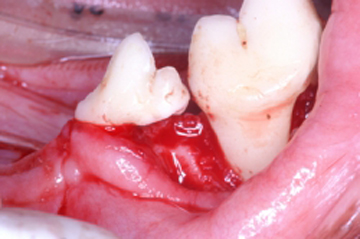

La periodontitis se clasifica como “Periodontitis leve” cuando el tejido óseo se ha destruido máximo en el tercio cervical; “Periodontitis moderada” cuando la destrucción ósea ha llegado al tercio medio de la raíz y “Periodontitis severa” cuando la destrucción ósea ha llegado al tercio apical de la raíz. La movilidad dental ligera aparece en la periodontitis moderada y la movilidad dental excesiva aparece en la periodontitis severa.

Haz CLICK sobre la imagen para ver descripción.